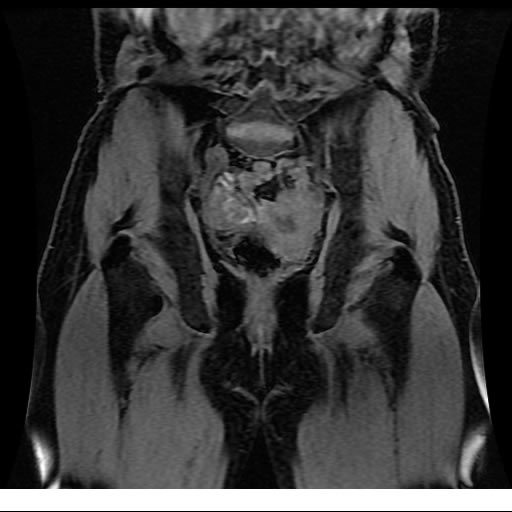

Se realizan adquisiciones en diferentes planos, con secuencias Spin echo y GRE, ponderadas a T1 y a T2, se utilizan pulsos de saturación de grasa y se administra medio de contraste a base de gadolinio.

El útero está en retroversión, retroflexión, y en posición central, se observa liquido en la cavidad endometrial, debido a la presencia de un Ca endometrial; en el anexo derecho se observa una masa quística que mide 3.8 x 2.2 cm de diámetro, corresponde a un quiste bilobulado, posee pared gruesa con componente solido puede tratarse de un Cistoadenocarcinoma, el cual realza con el medio de contraste de forma importante, entra dentro de una clasificación O-Rad tipo IV compatible con un Cistoadenocarcinoma

O-RAD tipo IV, Cistoadenocarcinoma